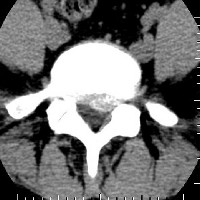

Sténose lombaire

Quand la compression n'est pas due à une hernie discale